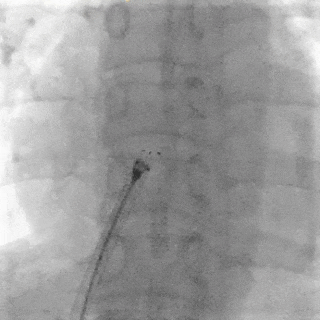

牵拉试验

牵拉试验封堵器整体移动不变形

锁定后封堵器呈工字型